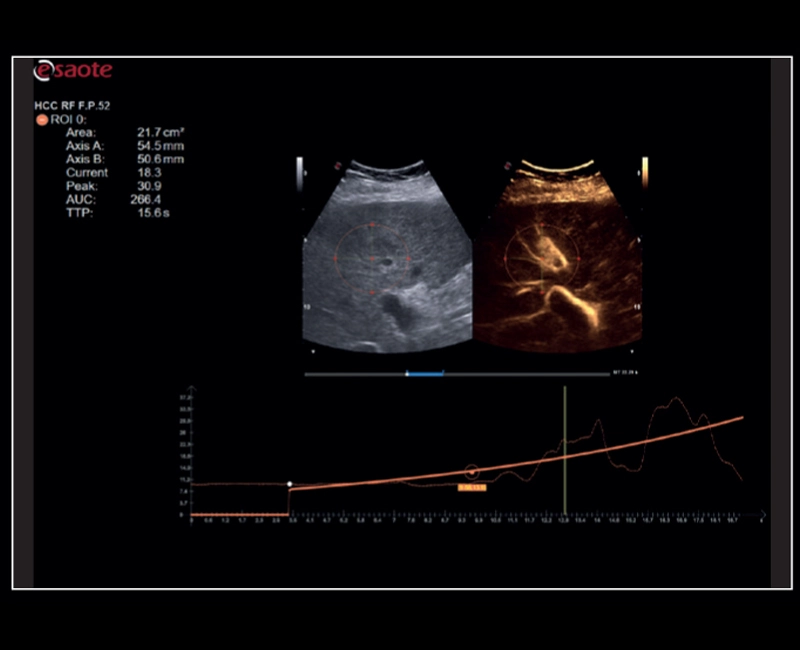

MyLab™9 Platform - QPack CnTI™ perfusion analysis post RF ablation

MyLab™9 Platform - QPack CnTI™ perfusion analysis post RF ablation